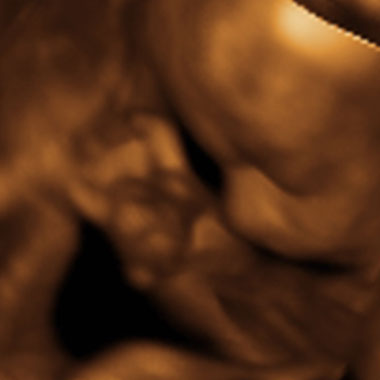

Baby #3's 3D Ultrasound 24

20.06.2007 15:10 |